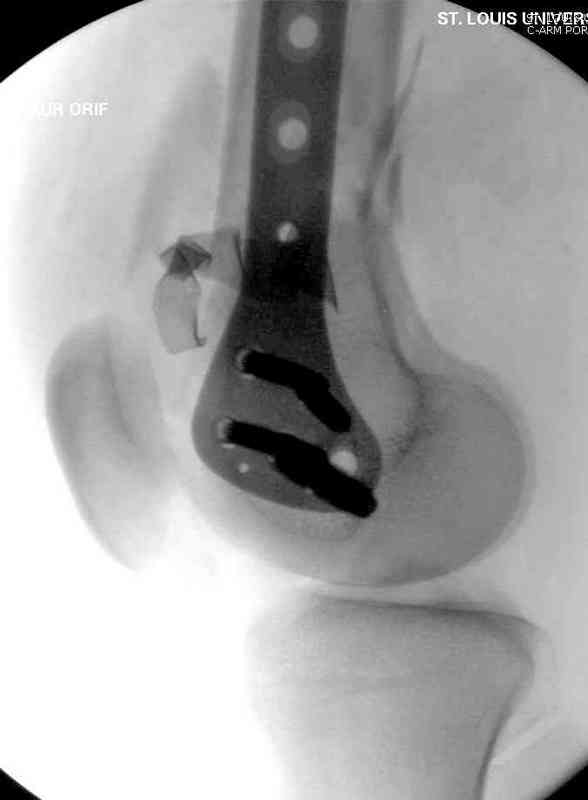

Вчера утром поступил больной с огнестрельной раной, осмотрен сосудистым специалистом, сделана ангиограмма (снимки) Во время операции при вскрытии обнаружили кровотечение, рану забили салфетками, установили пластину locking DePuy.

Из-за возрастающего давления в компартменте сделана фасциотомия и вызванный сосудистый хирург ушил разрыв вены на уровне перелома. Все раны оставлены открытими, в пятницу закроем.